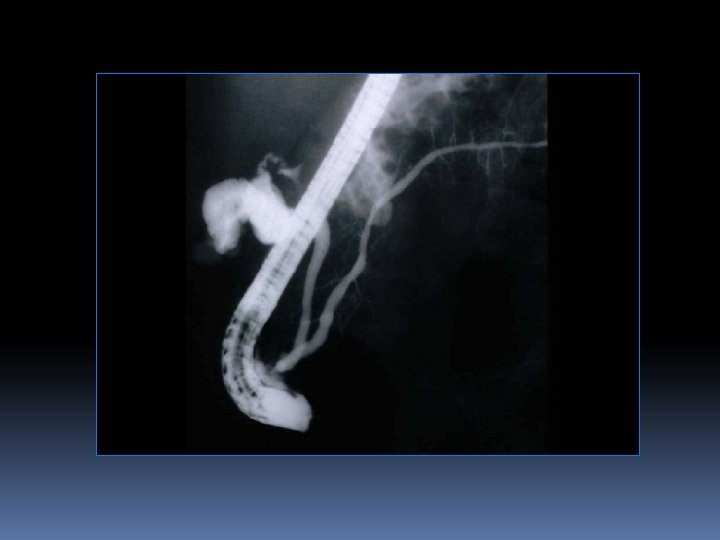

E- cholangio-pancreatographie rétrograde endoscopique ( CPRE): Technique: Sous AG 2 temps: endoscopique, repérage de papille radiologique, opacification canalaire rétrograde (biliaire et pancréatique) Intérêt: gestes thérapeutiques endoscopiques sphincterotomie+++ rarement diagnostique